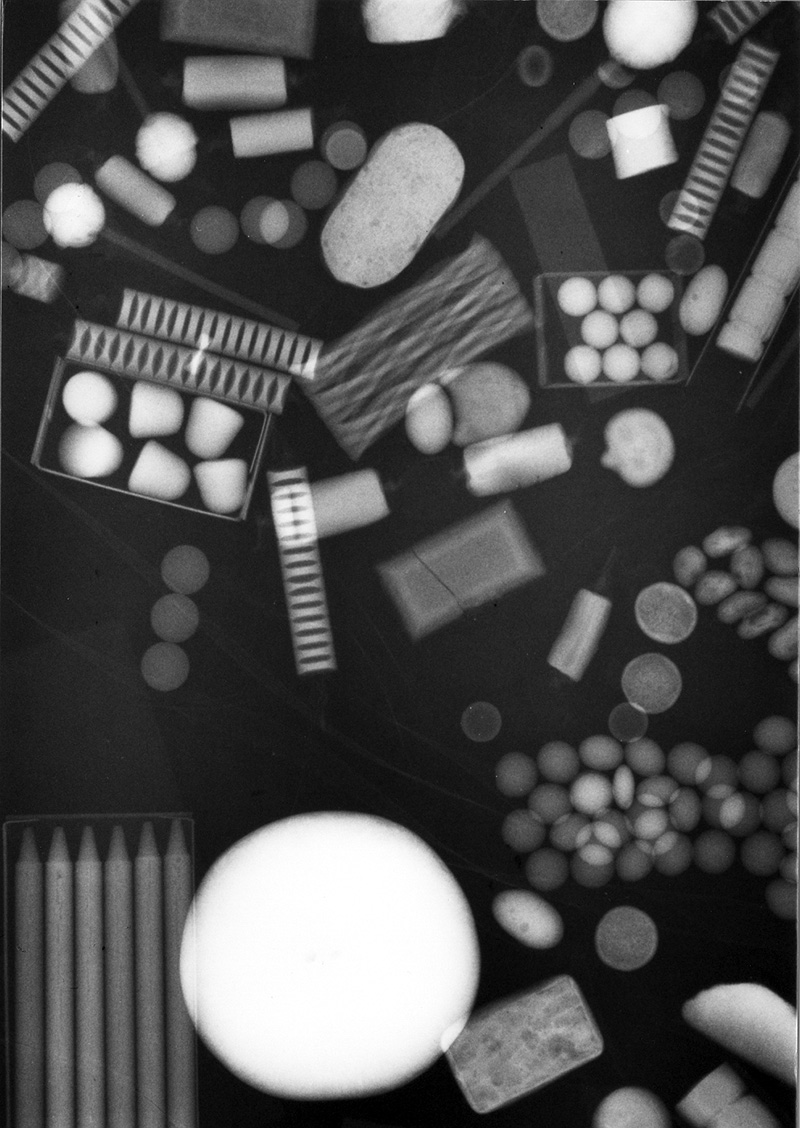

21 year-old man who injected himself with metallic mercury. There are mercury emboli to the lungs and metallic mercury is evident in the antecubital fossa of the left elbow. (Figures courtesy of Charles A. Rohrmann, Jr, MD. They were originally printed in Peterson, 1980). Trick or treat candy. There are no hidden needles or razor blades. The candy and the apple (round density) where eaten with much enjoyment. From Hunter, 1994

Halloween is a fun time of year for children. Unfortunately, some individuals have taken delight in hiding needles, razor blades, and other harmful items in candy and food given to trick or treaters. Radiography of food and candy is surprisingly effective (figure: halloween candy) and can be used to identify harmful objects or to reassure parents that there is a low likelihood for a sharp object lurking in treats.